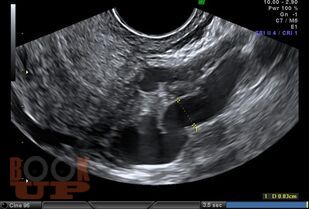

В пособии изложены современные принципы диагностики варикозной болезни вен таза. Представлена анатомия вен малого таза, этиопатогенез, классификация этого заболевания. Приводятся рекомендации о методологии инструментального исследования при этой патологии. Методические рекомендации предназначены для системы последипломного образования.